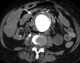

Aneurysm of abdominal aorta or its branches

The abdominal aorta is the largest artery in the abdominal cavity. As part of the aorta, it is a direct continuation of the descending aorta (of the thorax). [Source: Wikipedia ]